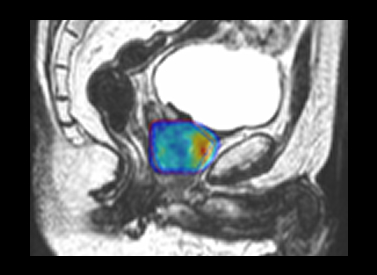

Elekta Unity’s Comprehensive Motion Management (CMM) with True

Tracking and Automatic Gating combines Unity’s diagnostic quality

imaging capabilities with powerful algorithms and technology to

quantify movement and correct for it automatically, as it

happens-ensuring precise and accurate treatment delivery.

Leveraging

the power of the 1.5 T MR, anatomy-specific imaging sequences optimize

the visualization of the target and surrounding healthy tissue.